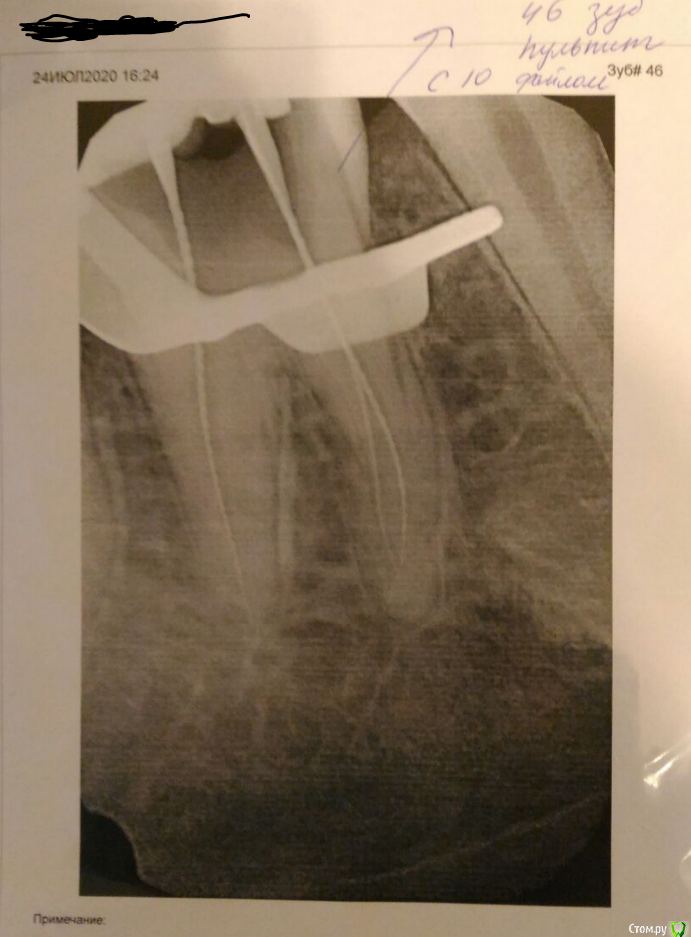

ValyaValya Опубликовано 24 июля, 2020 Поделиться Опубликовано 24 июля, 2020 Здравствуйте. Сегодня в стоматологии сделали рентгеновский снимок, врач сказал пульпит. При этом ноющих болей в зубе не было. Можете подтвердить/опровергнуть диагноз по снимку, если это возможно? Ссылка на комментарий

ValyaValya Опубликовано 24 июля, 2020 Автор Поделиться Опубликовано 24 июля, 2020 сам снимок Ссылка на комментарий

ValyaValya Опубликовано 24 июля, 2020 Автор Поделиться Опубликовано 24 июля, 2020 До лечения нет, к сожалению. Когда врач попытался вычистить глубокий кариес под пломбой, оказалось, что зуб вскрылся. В этот момент и сделали снимок Ссылка на комментарий

Dr.Ru Опубликовано 24 июля, 2020 Поделиться Опубликовано 24 июля, 2020 Когда врач попытался вычистить глубокий кариес под пломбой, оказалось, что зуб вскрылся.Бывает такое при глубоком кариесе. 1 Ссылка на комментарий